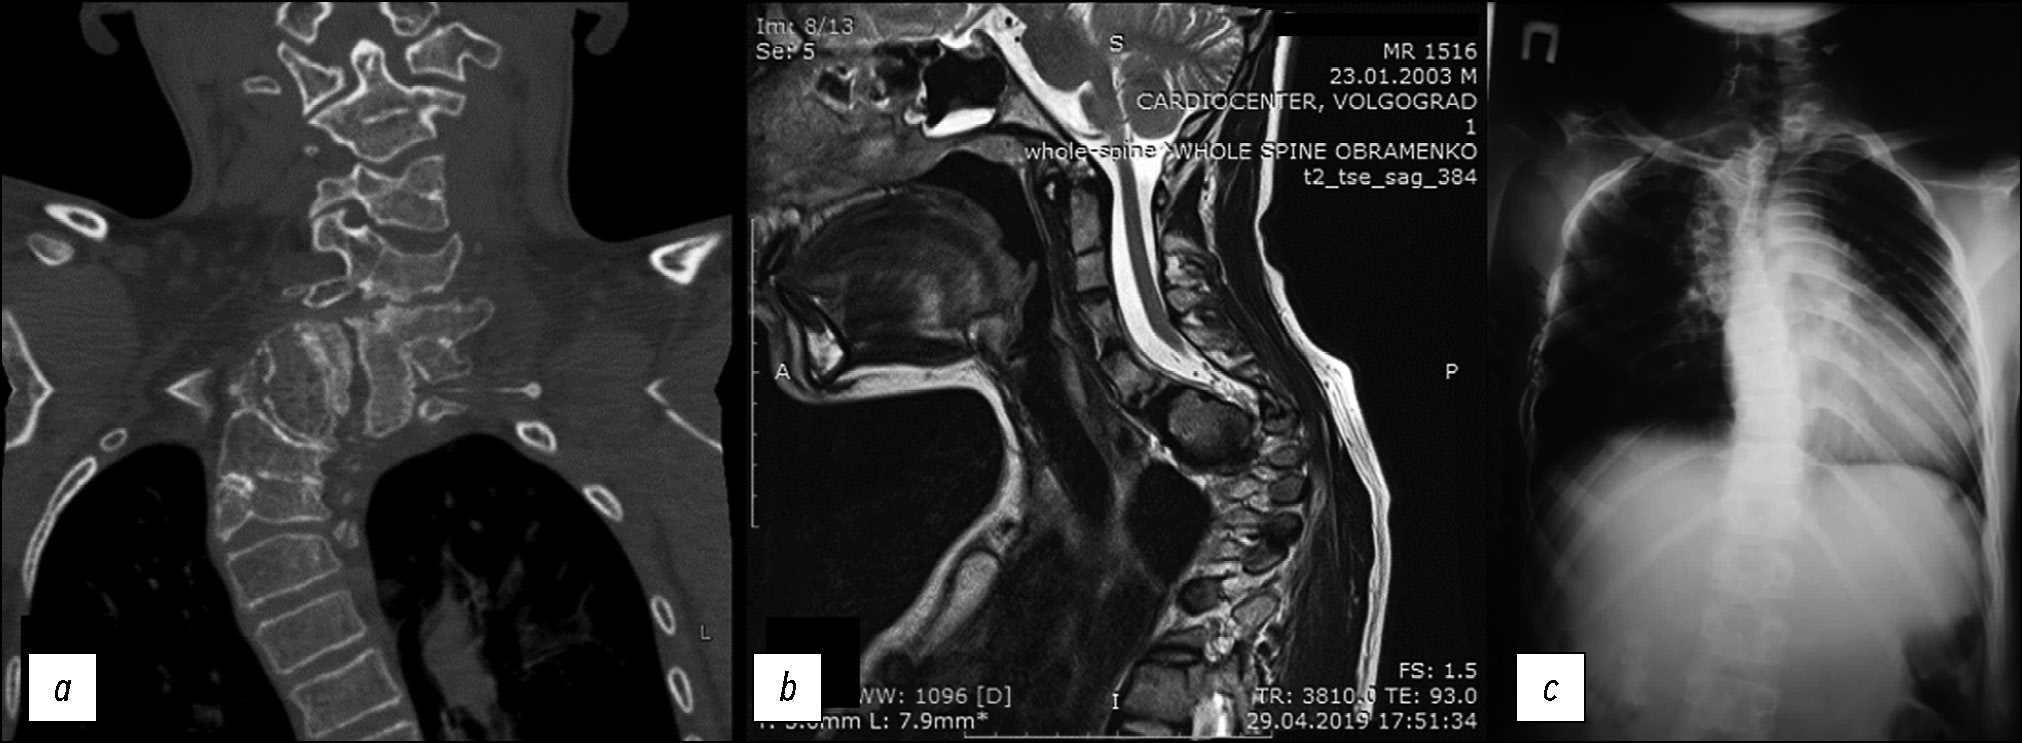

Пациенту выполнены диагностические исследования: компьютерная томография (КТ), магнитно-резонансная томография (МРТ) и рентгенограмма шейно-грудного отдела позвоночника (в прямой и боковой проекции) (рис. 1).

Рис. 1. Компьютерная томография (a), магнитно-резонансная томография (b) и рентгенограмма (c) шейно-грудного отдела позвоночника. По данным КТ и МРТ выявлен стеноз позвоночного канала С4–Тh4 с МР-признаками миелопатии. По данным КТ и рентгенографии позвоночника картина врождённой аномалии позвоночника следующая: заднебоковой клиновидный добавочный полупозвонок С7, локальный угловой кифоз на уровне С6–7 позвонка с наличием костного блока тел и задних элементов Th1–3 позвонков и заднебоковым клиновидным полупозвонком Th4–Th5.

Fig. 1. Computed tomography (a), magnetic resonance imaging (b) and radiograph (c) of the cervicothoracic spine. CT and MRI data revealed stenosis of the C4–Th4 spinal canal with MR signs of myelopathy. According to CT and radiography of the spine, the picture of the congenital anomaly of the spine is as follows: posterolateral wedge-shaped accessory hemivertebra C7, local angular kyphosis at the level of the C6–7 vertebra with the presence of a bone block of the bodies and posterior elements of the Th1–3 vertebrae and a posterolateral wedge-shaped hemivertebra Th4–Th5.

Пациент С., поступил в 14-е отделение вертебрологии НМИЦ ТО им. Н.Н. Приорова в возрасте 15 лет с жалобами на невозможность самостоятельной ходьбы и опоры на нижние конечности, деформацию позвоночника. Из анамнеза известно, что с двухлетнего возраста больной наблюдается у ортопеда по поводу сколиотической деформации грудного отдела позвоночника (рис. 6). В 13 лет впервые отметил неуверенность походки с эпизодами падения. В течение последующего года появились деформация стоп и прогрессирующая слабость в ногах. Пациент направлен на генетическое обследование. Выполнено секвенирование клинического экзома 6640 генов, выявлен вариант нуклеотидной последовательности в экзоне 11-го гена SH3TC2 в гетерозиготном состоянии. В экзоне 15-го гена SH3TC2 выявлен ранее не описанный вариант нуклеотидной последовательности в гетерозиготном состоянии, мутации в гене SH3TC2 расценены как патогенные. Данные мутации характерны для пациентов с болезнью Шарко–Мари–Тута, тип 4С. В анамнезе также выявлен синдром ночного апноэ с эпизодами снижения сатурации до SpO2=88%. По электронейромиографии нижних конечностей выявлено снижение скорости проведения по нервам ниже 22 м/с.

Рис. 6. Постуральная рентгенография позвоночника в возрасте двух лет жизни.

Fig. 6. Postural radiography of the spine at two years of age.

По данным постуральной рентгенографии позвоночника в двух проекциях: картина левостороннего кифосколиоза грудного отдела позвоночника IV степени, угол Cobb сколиотической дуги 90° с вершиной Th6–7, угол кифотической дуги 115° с вершиной Th6–7 (рис. 7).

Рис. 7. Постуральная рентгенография позвоночника на момент поступления.

Fig. 7. Postural radiography of the spine at the time of admission to hospital